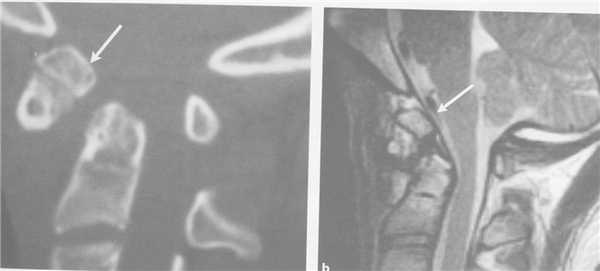

(Слева) Сагиттальный КТ-срез (костный режим) подчеркивает важность дальнейшего обследования пациента с травмой при минимальных или неопределенных изменениях на КТ. Отмечается небольшое расширение переднего отдела межтелового промежутка С6-С7 и отек превертебральных мягких тканей.

(Справа) На сагиттальном STIR МР-И определяются явные признаки гиперэкстензионной травмы на уровне С6-С7 в виде разрыва ППС, патологического усиления сигнала межпозвонкового диска и распространенного отека/кровоизлияний в превертебральных тканях. (Слева) КТ, сагиттальный срез (костный режим): гиперэкстензионное повреждение шейного отдела позвоночника с расширением межтелового пространства C4-C5 и переломом в области пластинки дуги и остистого отростка.